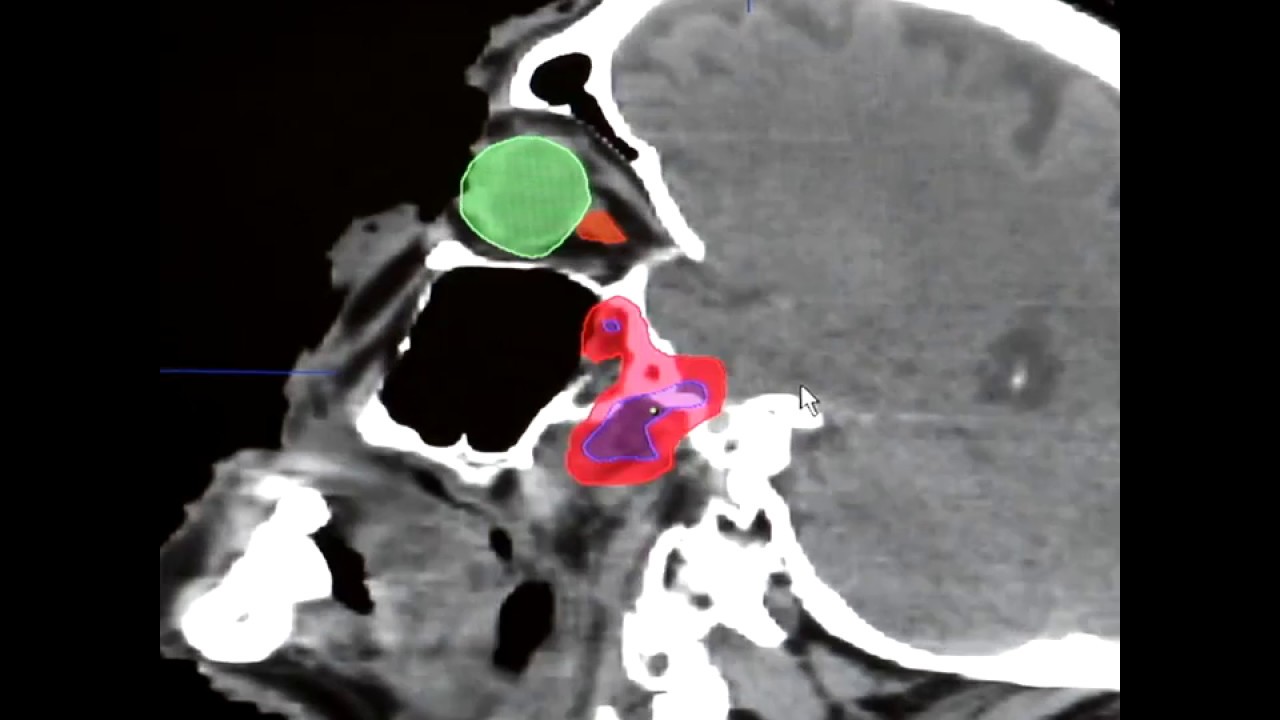

CT Scan

Описание: A CT scan is used to examine patients with brain trauma or disease, but can also be useful in viewing other areas of the body.